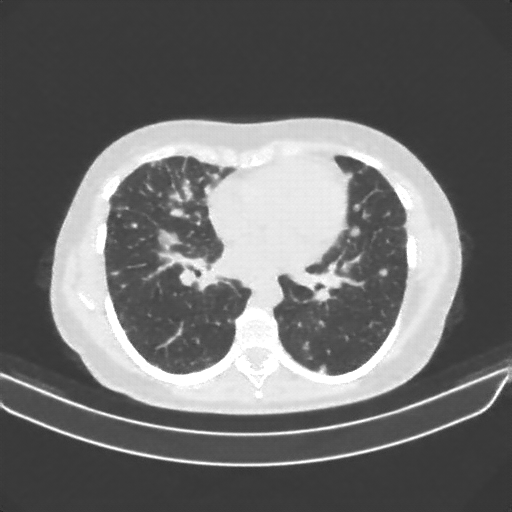

Slice 70 Targeting Evaluation

Slice: Slice_70

Conversion: NATIVE β†’ VENOUS

Original VENOUS CT scan

No window - Raw intensity values

Lung window (WL -600, WW 1500 β†’ Low βˆ’1350, High +150)

Mediastinum window (WL 40, WW 400 β†’ Low βˆ’160, High +240)

Targeted Slice 70 - HU-Space Analysis (Generated vs Real Venous)

0.845

HU SSIM

120.9

HU RMSE

54.7

HU MAE